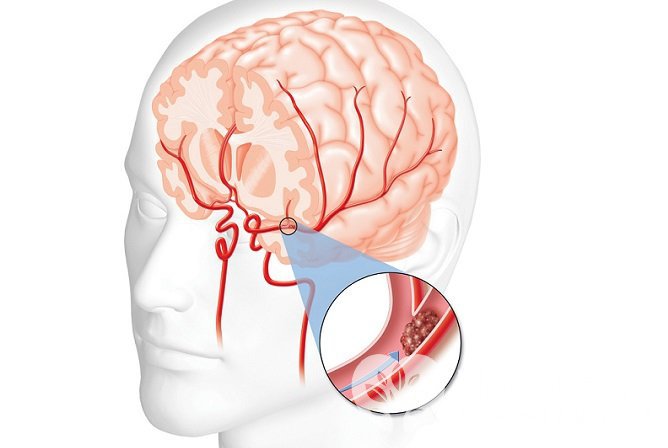

Ишемический инсульт вызывается блокированием кровотока в одной из мозговых артерий

Ишемический инсульт вызывается блокированием кровотока в одной из мозговых артерийНеврологические нарушения, приводящие к инвалидности, в течение первого месяца после перенесенного инсульта отмечаются у 60-70% пациентов, спустя полгода – у 40%, спустя год – у 30%. Лучшая динамика реабилитации наблюдается в первые три месяца. Если нарушенные функции не удалось восстановить в течение года, в дальнейшем их восстановление маловероятно.

Ранняя диагностика и начало лечения улучшают прогноз при инсульте

Ранняя диагностика и начало лечения улучшают прогноз при инсультеШкалы индивидуальной оценки риска